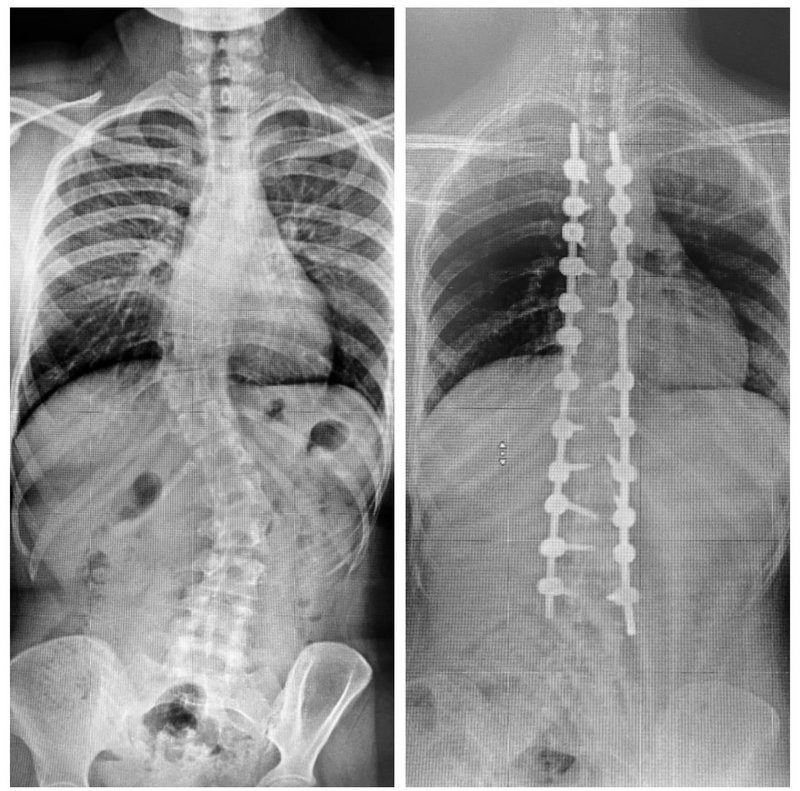

وأضاف أن المريضة وصلت للمستشفى برفقة ذويها تشكو من انحناء حاد في العمود الفقري، يصاحبه آلام حادة ومتكررة مع صعوبة التبول، بالإضافة إلى مشاكل دائمة في التنفس؛ مشيرًا إلى أنه تم إخضاع المريضة لكل التحاليل المخبرية وفحوصات دقيقة بالرنين المغناطيسي (M.R.I) والتصوير المقطعي (C.T Scan)، وقد أبانت الفحوصات أن وضع المريضة يعد من الحالات المعقدة جدًّا، نظرًا لوجود اعوجاجين؛ الأول ناحية الصدر نسبته 55 درجة، أما الانحراف الثاني أسفل الظهر بنسبة 40 درجة.

وعن العملية أفاد استشاري جراحة المخ والأعصاب والعمود الفقري بأن الفريق الطبي المعالج قرر التدخل الجراحي بعد مراجعة دقيقة لكل المعطيات الطبية، موضحًا أن العملية استغرقت 6 ساعات متواصلة، وتم فيها تعديل الانحرافين بنجاح تام عبر استخدام أحدث التقنيات وأدوات تثبيت الفقرات والمصنّعة من مادة التيتانيوم والكوبلت.